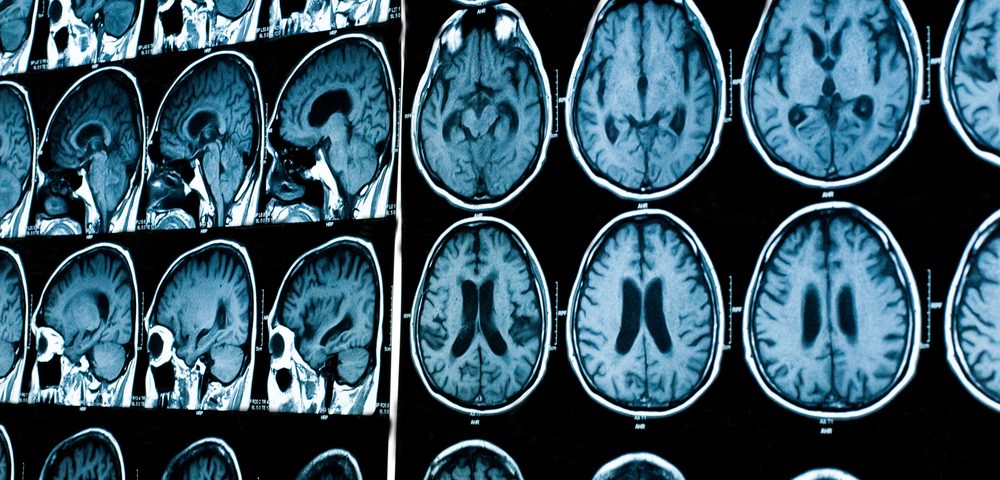

आपला मेंदू आणि मानसशास्त्राचा अभ्यास करणाऱ्या विज्ञानाच्या न्युरोसायकॉलॉजी शाखेनं याबाबत अभ्यास केला. मेंदूचा आपल्या स्वभावावर आणि भावनांवर कसा परिणाम होतो हे त्यांनी तपासलं. या अभ्यासातून असं लक्षात आलं की मेंदूचा प्रत्येक भाग शरीराच्या वेगवेगळ्या कार्याशी निगडीत असतो. ‘पॉझिट्रॉन एमिशन टोमोग्राफी’ आणि ‘फंक्शनल मॅग्नेटिक रेजोनेंस इमेजिंग’ या दोन आधुनिक तंत्रांमुळे मेंदूचा सखोल अभ्यास करता येतो. या पद्धतीचा वापर करून हे सिद्ध करण्यात आलंय की मानवी शरीराची हालचाल आणि त्याच्या रोजच्या कामं नियंत्रित करणारा मेंदू या दोन गोष्टी वेगळ्या करताच येत नाहीत. म्हणजे आता उदाहरणच द्यायचं झालं तर, जेव्हा आपण चॅट करतो, तेव्हा ३ गोष्टींवर नियंत्रण असलेले मेंदूतीलले विभाग सर्वात जास्त कार्यरत असतात. हे तीन विभाग म्हणजे डोळे, हात नियंत्रण करणारी व दृश्य समजून घेणारी बाजू. डोळ्यांनी दिसणारं दृश्य समजून घेऊन त्याच्यानुसार प्रतिक्रिया देण्यासाठी मेंदूच्या एका विशिष्ट विभागाचा वापर होतो. तर मोबाईल पकडण्यासाठी हातांवर नियंत्रण असलेला मेंदूचा विभाग यावेळी कार्यरत असतो. याचाच अर्थ मेंदूचा कोणताही भाग निष्क्रिय नसतो. मेंदूच्या प्रत्येक मज्जातंतूला आपापलं काम वाटून देण्यात आलेलं असतं.

आपण काम करत असताना त्या कामासाठी लागणारा मेंदूचा भाग कसा कार्यरत असतो हे मेंदूच्या आतल्या छायाचित्रांमधून दिसून आलेलं आहे. मेंदूच्या या फोटोंमध्ये काही ठळक चट्टे दिसून आलेत. हे चट्टे दाखवतात की मेंदूचा तो भाग कार्यरत आहे. त्याच्या विरुध्द इतर भाग अस्पष्ट दिसतात. याचं करणं म्हणजे तो भाग कार्यरत आहे, पण इतर भागांच्या तुलनेत कमी काम करत आहे. मेंदूला ‘प्लास्टिक ब्रेन’ म्हटलं जातं. आता प्लास्टिकचा शब्दशः अर्थ घेऊ नका राव. इथे प्लास्टिकचा अर्थ ‘लवचिक’. आपल्या कामाप्रमाणे आपल्या मेंदूचा विशिष्ट भाग इतर भागांपेक्षा जास्त विकसित होतो. म्हणजे असं बघा, बस चालकांपेक्षा टॅक्सी किंवा रिक्षा चालकांच्या मेंदूचा दिशा समजून घेण्याचा भाग जास्त विकसित झालेला आढळला आहे. कारण त्यांना शहरातील सगळेच रस्ते लक्षात ठेवावे लागतात. जसं आपल्या व्यायामाने व आहाराने शरीर घडत जातं तसंच आपल्या कामाने मेंदू घडत जातो.